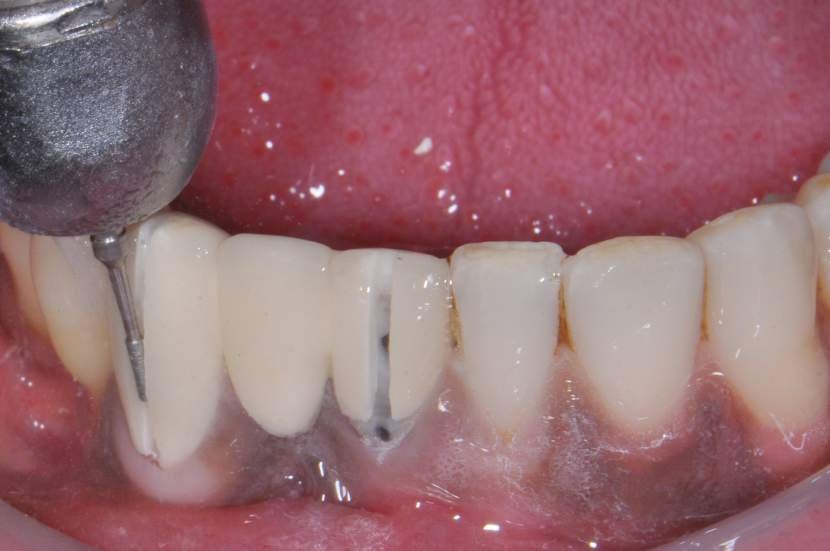

O procedimento cirúrgico para os implantes Slim segue um protocolo semelhante como outros implantes, porém muito simplificado. Normalmente utilizase a técnica anestésica infiltrativa. Um retalho mucoperiosteal deve ser rebatido para uma observação direta do rebordo ósseo disponível. No entanto, quando o tecido queratinizado e o volume ósseo abundantes estiverem presentes, uma cirurgia flapless é muitas vezes o protocolo cirúrgico de escolha.2

Para instalação de implantes de Ø 2.5mm é necessário apenas a utilização da fresa lança diâmetro de 2.0 mm. E para instalação de implantes de 3.0 mm utilização da fresa lança diâmetro de 2.0 mm e opcionalmente a fresa Countersink Slim 3.0mm (em casos de osso tipo I ou tipo II). O implante tem o ápice cortante e espiras que facilitam sua instalação. Os implantes Slim se apresentam de 1 em 1 mm de comprimento de 7 a 13 mm, o que facilita muito a escolha dos tamanhos no momento do planejamento.